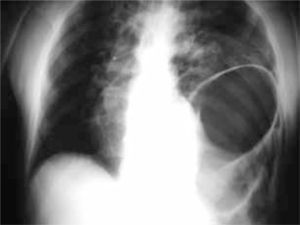

Estudios radiológicos simples: son parte del protocolo de manejo y puedan dar información directa como ruptura de un hemidiafragma o neumoperitoneo, o indirecta como fracturas de columna lumbar o de las costillas inferiores, que nos orientan hacia algunas lesiones (3, 8-11).

Radiología simpleAyuda a determinar la trayectoria de las balas, lo que se facilita marcando los orificios en la piel con marcadores radiopacos (10). También ayuda a ubicar el proyectil si no hay salida, lo que hace sospechar las lesiones causadas. Debemos recordar que el proyectil puede ingresar al cuerpo por un área distinta al abdomen y sin embargo lesionarlo. Se debe sospechar de los proyectiles que ingresan en cualquier área desde el cuello hasta la porción media de los muslos (3). Ayuda a detectar neumoperitoneo, fracturas de columna, neumo o hemotórax (9, 10).